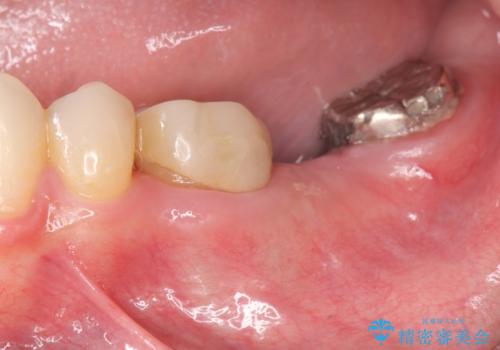

最後方臼歯のインプラント補綴

最後方臼歯の治療について

最後方臼歯を喪失した場合、入れ歯・インプラントによる咬合機能回復方法があります。

今回はしっかりと噛むことができ、取り外しの必要のないインプラントによる補綴を行いました。